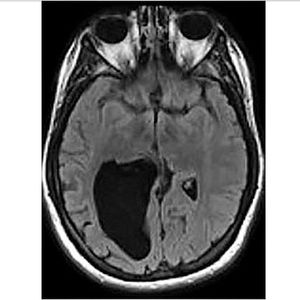

Cole Cohen struggled with math, keeping time, getting lost, couldn't judge how far away a car was when she crossed the road, and had a hard time with all kinds of things. Her parents took her to doctor after doctor, and there were all kinds of tests and experiments with medication, but no real diagnosis. She was told she had "learning difficulties" and was put on medication for Attention Deficit Disorder (ADD). Eventually, at the age of 26, after doing an MRI (the image above) she found out she had a large black mass on an image of her brain, a hole in her brain the size of a lemon! The hole was filled with brain and spinal fluid (cerebrospinal fluid), leading to problems with her parietal lobe - which controls sense of space, understanding numbers, sensory information and navigation. "Just because I have a hole in my brain doesn't mean I have a hole in my mind" She says. "Or does it?" She has written a book which documents her journey - Head Case: My Brain and Other Wonders. Today, she's undergoing a type of brain training to strengthen her thinking skills.